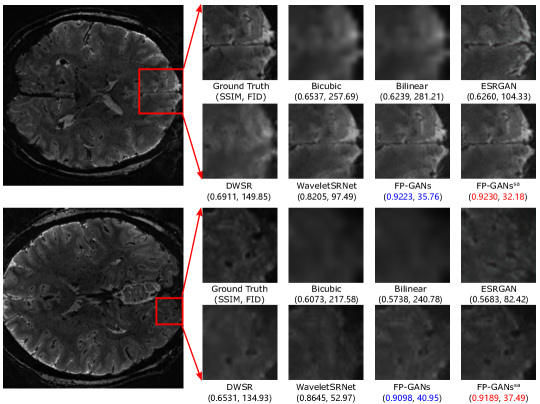

Figure 6: Visual comparison of detail recovery performance on MultiRes_7T dataset. The images are gained with super-resolution scale factor ×4absent4\times 4. Red and blue indicate the best and the second best performance, respectively.

As illustrated in Figure 6, the interpolation based methods produce over-smooth results. GAN based method—ESRGAN reproduces rich textures though, the result loses its coherency with the input. FP-GANs recovers finer anatomical structure with shaper and clearer textures while remaining consistency. To further examine the detail capture ability, difference heatmap, reflecting absolute difference between generated image and corresponding ground truth, is utilized as Figure 7 shows. It can be apparently observed that there is less difference in the heatmap of FP-GANs and FP-GANssa than the competing methods. This confirms the detail sensitivity of the proposed structure.